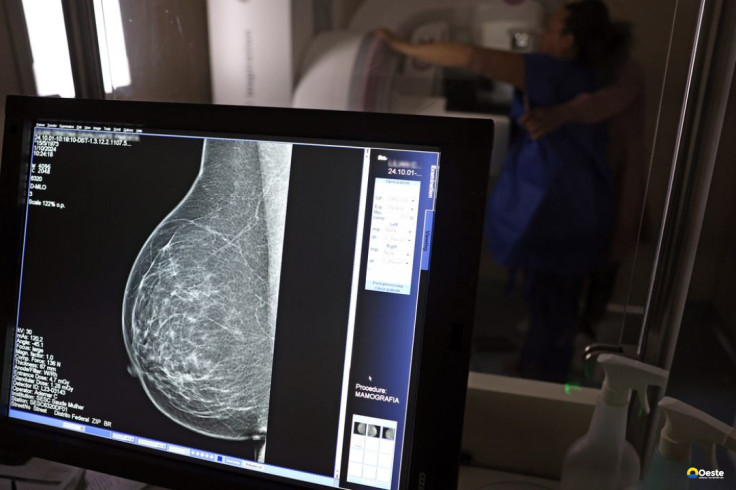

Ministério da Saúde passa a recomendar mamografia a partir dos 40 anos

Até então, a orientação era que o exame fosse feito a partir dos 50 anos.

A medida faz parte de um conjunto de ações anunciadas nesta terça-feira (23) voltado para a melhoria do diagnóstico e da assistência. A recomendação para mulheres a partir dos 40 anos é que o exame seja feito sob demanda, em decisão conjunta com o profissional de saúde.

As mamografias via SUS em pacientes com menos de 50 anos, de acordo com a pasta, representam 30% do total, o equivalente a mais de 1 milhão apenas no ano de 2024.

Outra medida anunciada é a ampliação da faixa etária para o rastreamento ativo – quando a mamografia é solicitada de forma preventiva a cada dois anos. A idade limite, até então, era 69 anos. Agora, passa a ser 74 anos. Dados do ministério revelam que quase 60% dos casos de câncer de mama estão concentrados entre 50 e 74 anos.

“A ampliação do acesso à mamografia aproxima o Brasil de práticas internacionais, como as adotadas na Austrália, e reforça o compromisso em garantir diagnóstico precoce e cuidado integral às mulheres brasileiras. O câncer de mama é o mais comum e o que mais mata mulheres, com 37 mil casos por ano”, reforçou a pasta.

Os números mostram que, em 2024, cerca de 4 milhões de mamografias para rastreamento e 376,7 mil exames diagnósticos foram realizados no SUS.